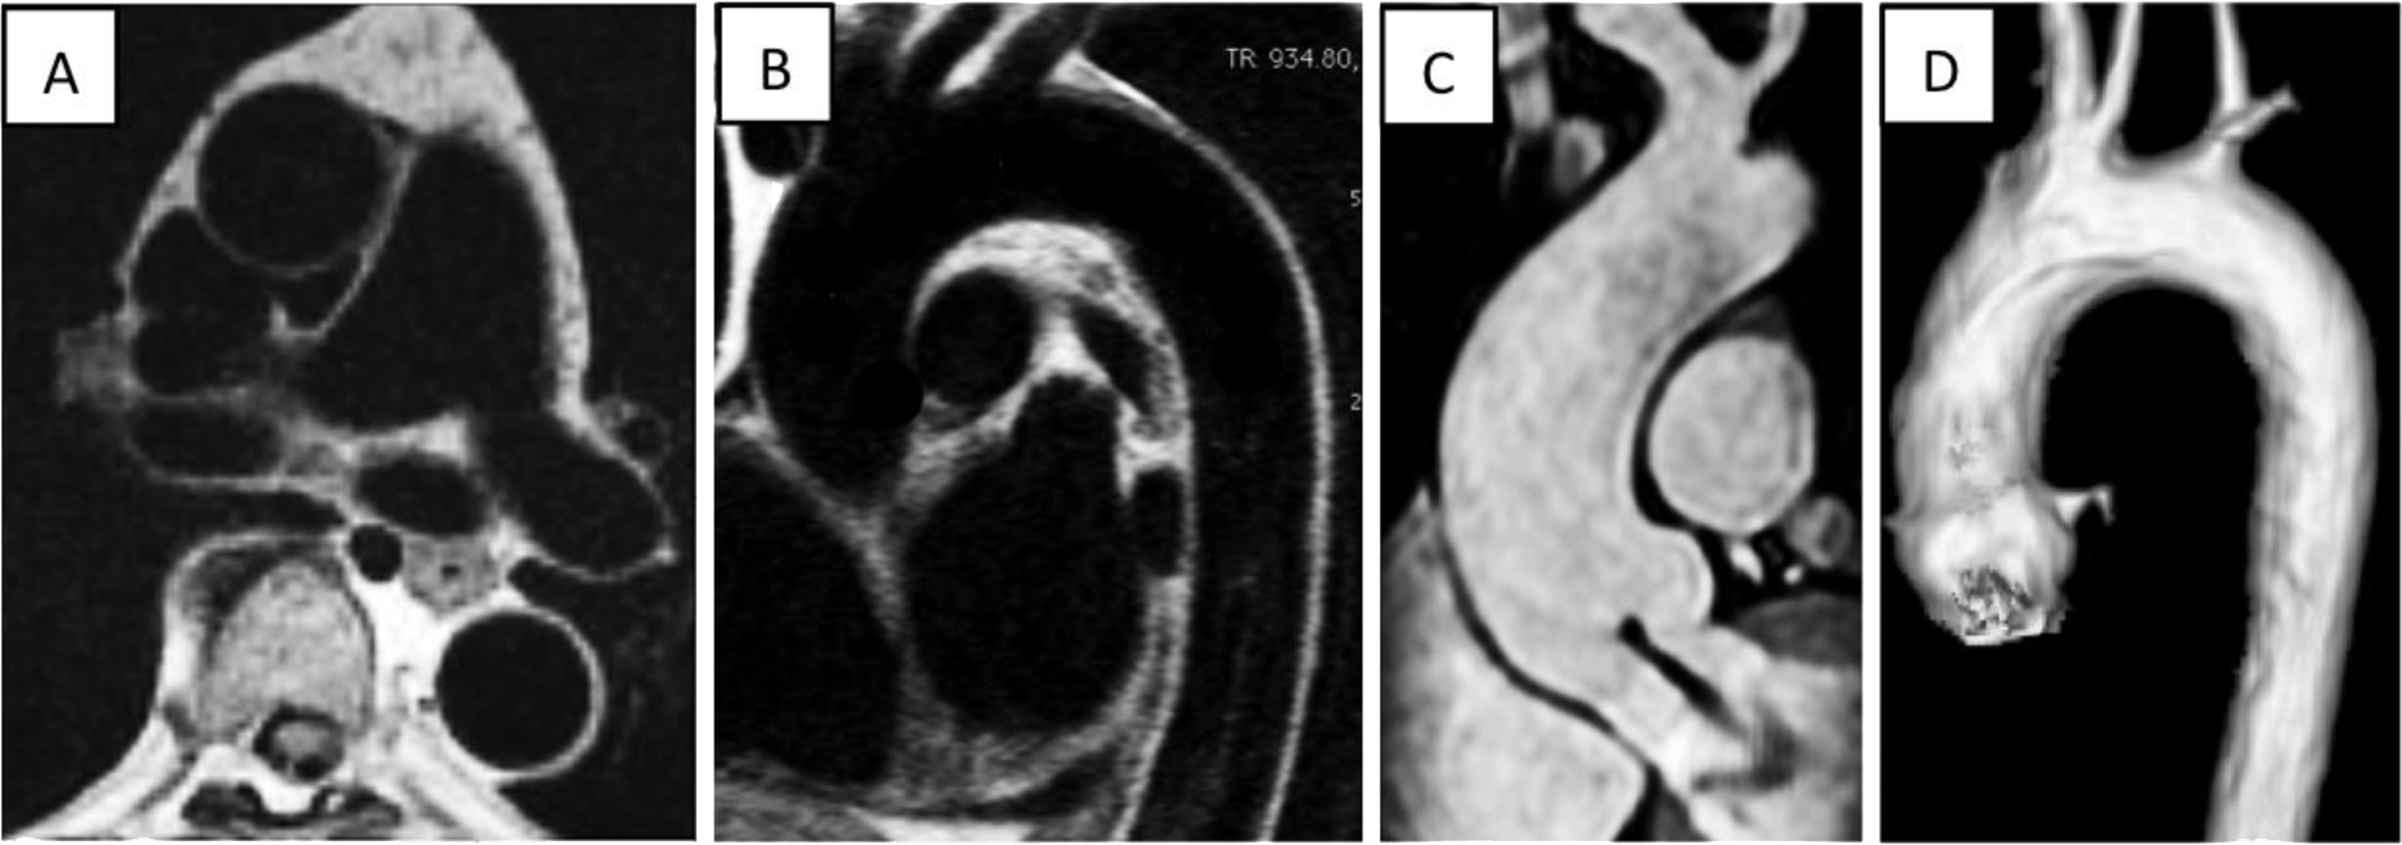

MRI, a reference technique to evaluate cardiac structure and function also uniquely provides non-invasive depiction of aortic anatomy, wall motion and flow in any given anatomical localization or spatial direction. Electrocardiogram gating and segmented acquisition techniques over several heartbeats are used to generate anatomic images corresponding to different phases of the cardiac cycle. The resulting cine acquisitions can be used to track aortic wall motion with high spatial (0.7 mm) and temporal resolution (10 ms–30 ms) depending on the heart rate and breath holding ability. Moreover, the intrinsic sensitivity of magnetic resonance to motion and flow can be used to produce velocity and flow maps using phase-contrast acquisition sequences (Fig. 1).

Anatomy and geometry of the thoracic aorta in MRI. Cross sectional (panel A) and longitudinal sagittal oblique (panel B) views of the aorta in diastole in ECG-gated black-blood spin echo sequences allowing good depiction of the vessel wall. These sequences can be acquired prior to and after contrast injection. Reformat of a non-contrast 3-SSFP sequence (panel C) showing the ascending aorta and aortic root with central aortic regurgitation (linear signal void). Volume rendering of contrast enhanced 3D magnetic resonance angiography showing a normal “Roman” shaped aortic arch.